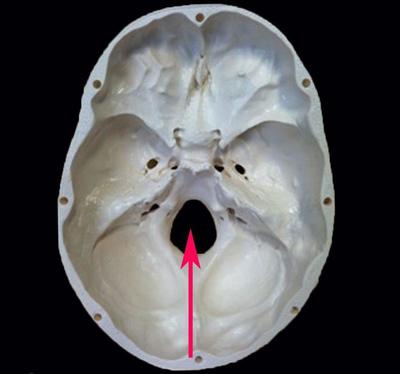

Question

La siguiente estructura señalada recibe el nombre de?

Answer

• Foramen magno

• Agujero rasgado

• Agujero mediano